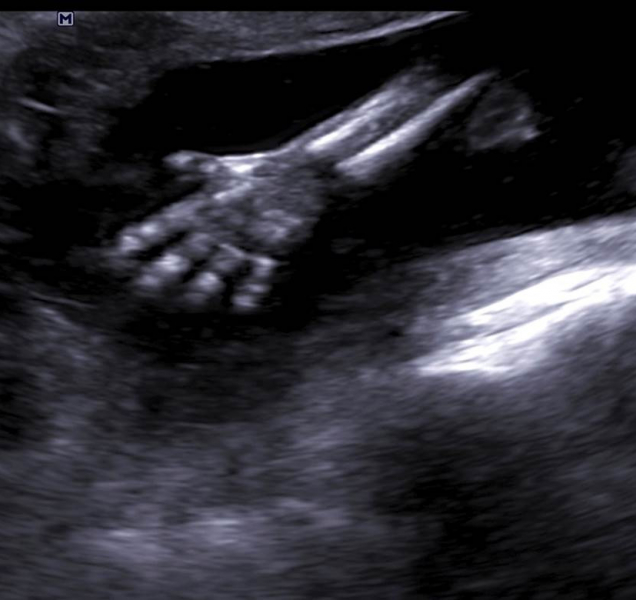

Do Olomouce se sjeli gynekologové z celé republiky